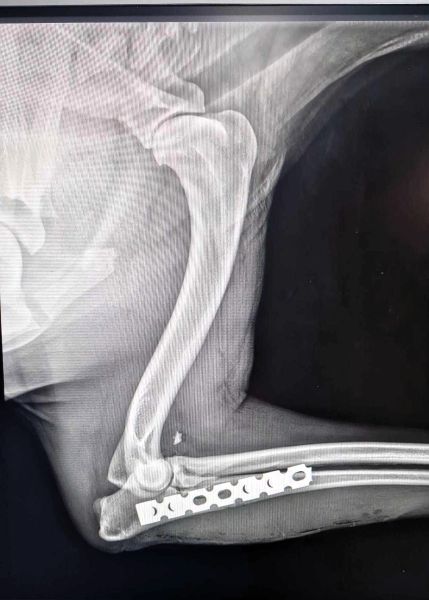

Diese nette Hündin wurde in Ploiesti vom Auto angefahren und ihr Bein wurde dabei gebrochen, sie ist aktuell in der Klinik und wird behandelt. Sie ist sehr freundlich und anfassbar. Schön wäre es, wenn sie direkt nach der Behandlung in ihr Für immer zu Hause reisen könnte.

| zur Besonderheit: | hatte Autounfall, Bein gebrochen |